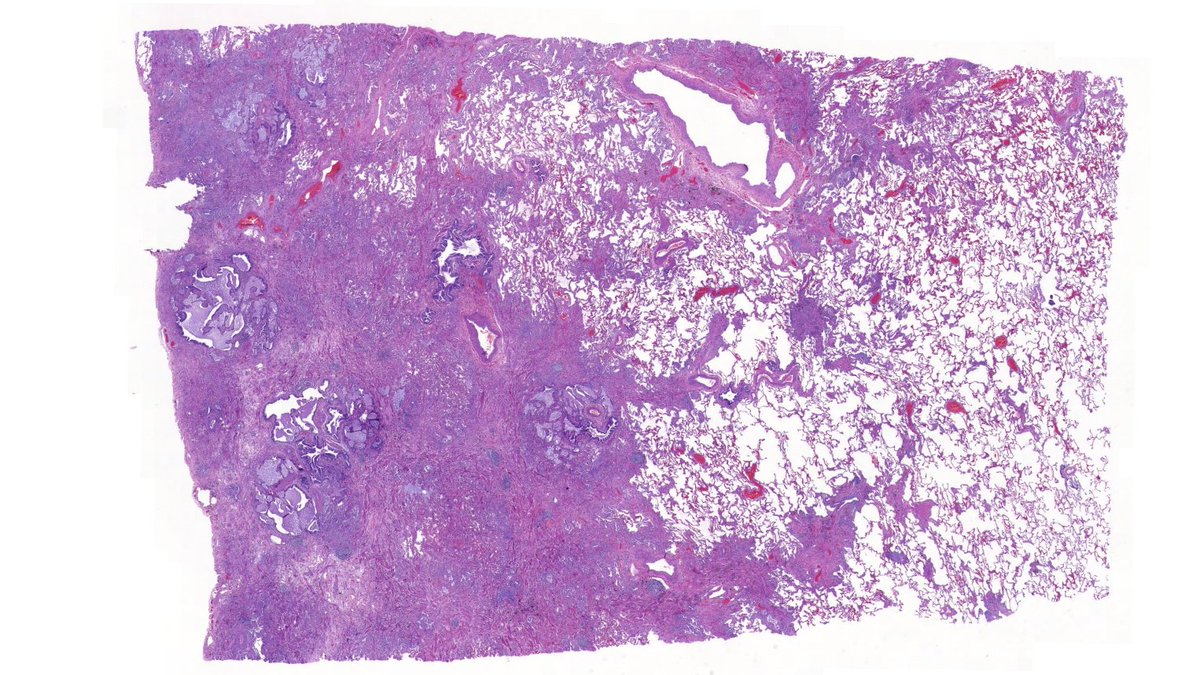

Explants from woman in her mid 40s. Clinical history on req: pulmonary hypertension. IHC is CD1a. Unifying diagnosis?

Thanks to all who engaged! Although uncommon, chronic LCH can lead to severe secondary pulmonary HTN which is what we see here. A spectrum of arterial lesions, including plexiform, dilatation, and medial hypertrophy. Wishing the patient a new lease on life with new lungs!